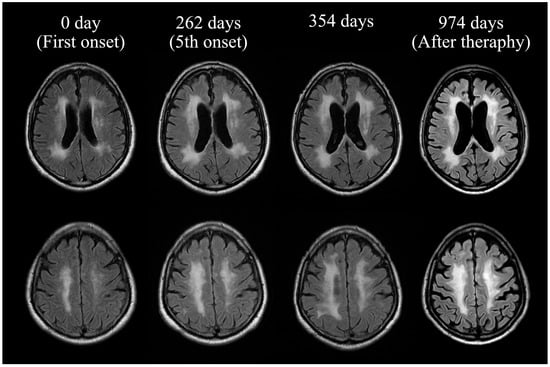

2. Case Presentation